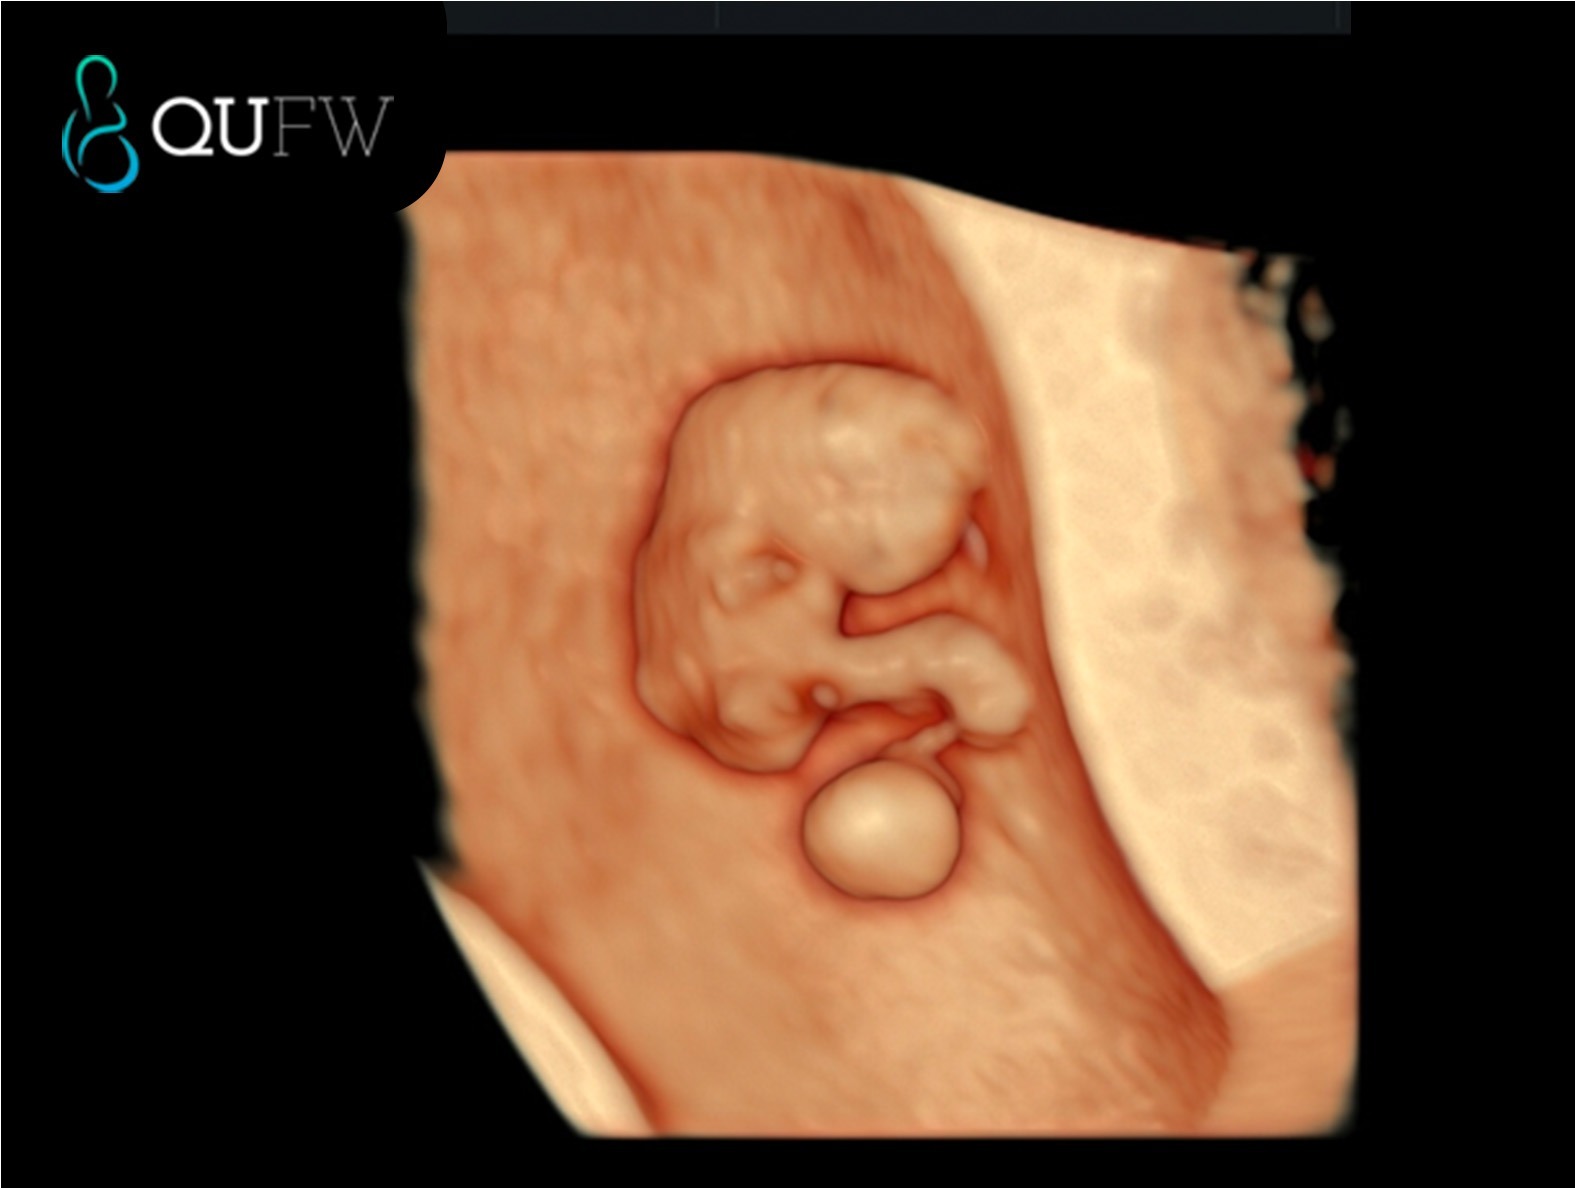

3D image of an 8 week fetus

8 week fetus with heartbeat